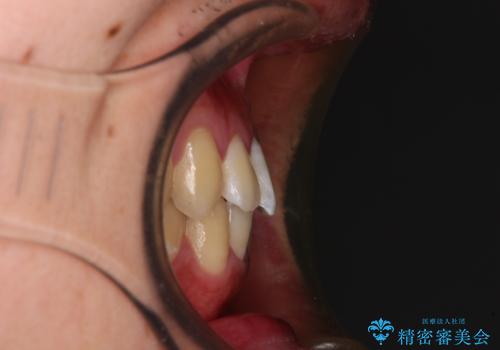

- 上下前歯のデコボコを気にして来院された患者様です。

叢生は軽微であり、費用を抑えて期間もあまりかけずに治療をしたいとのことで、インビザライン・ライトを用いて矯正治療を行うこととしました。